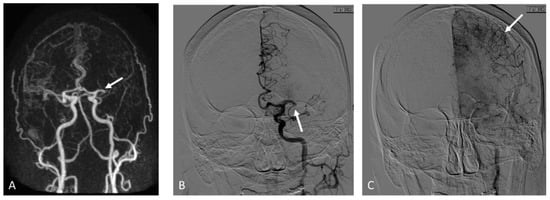

2. Materials and Methods

2.3.1. MRA

2.3.2. DSA